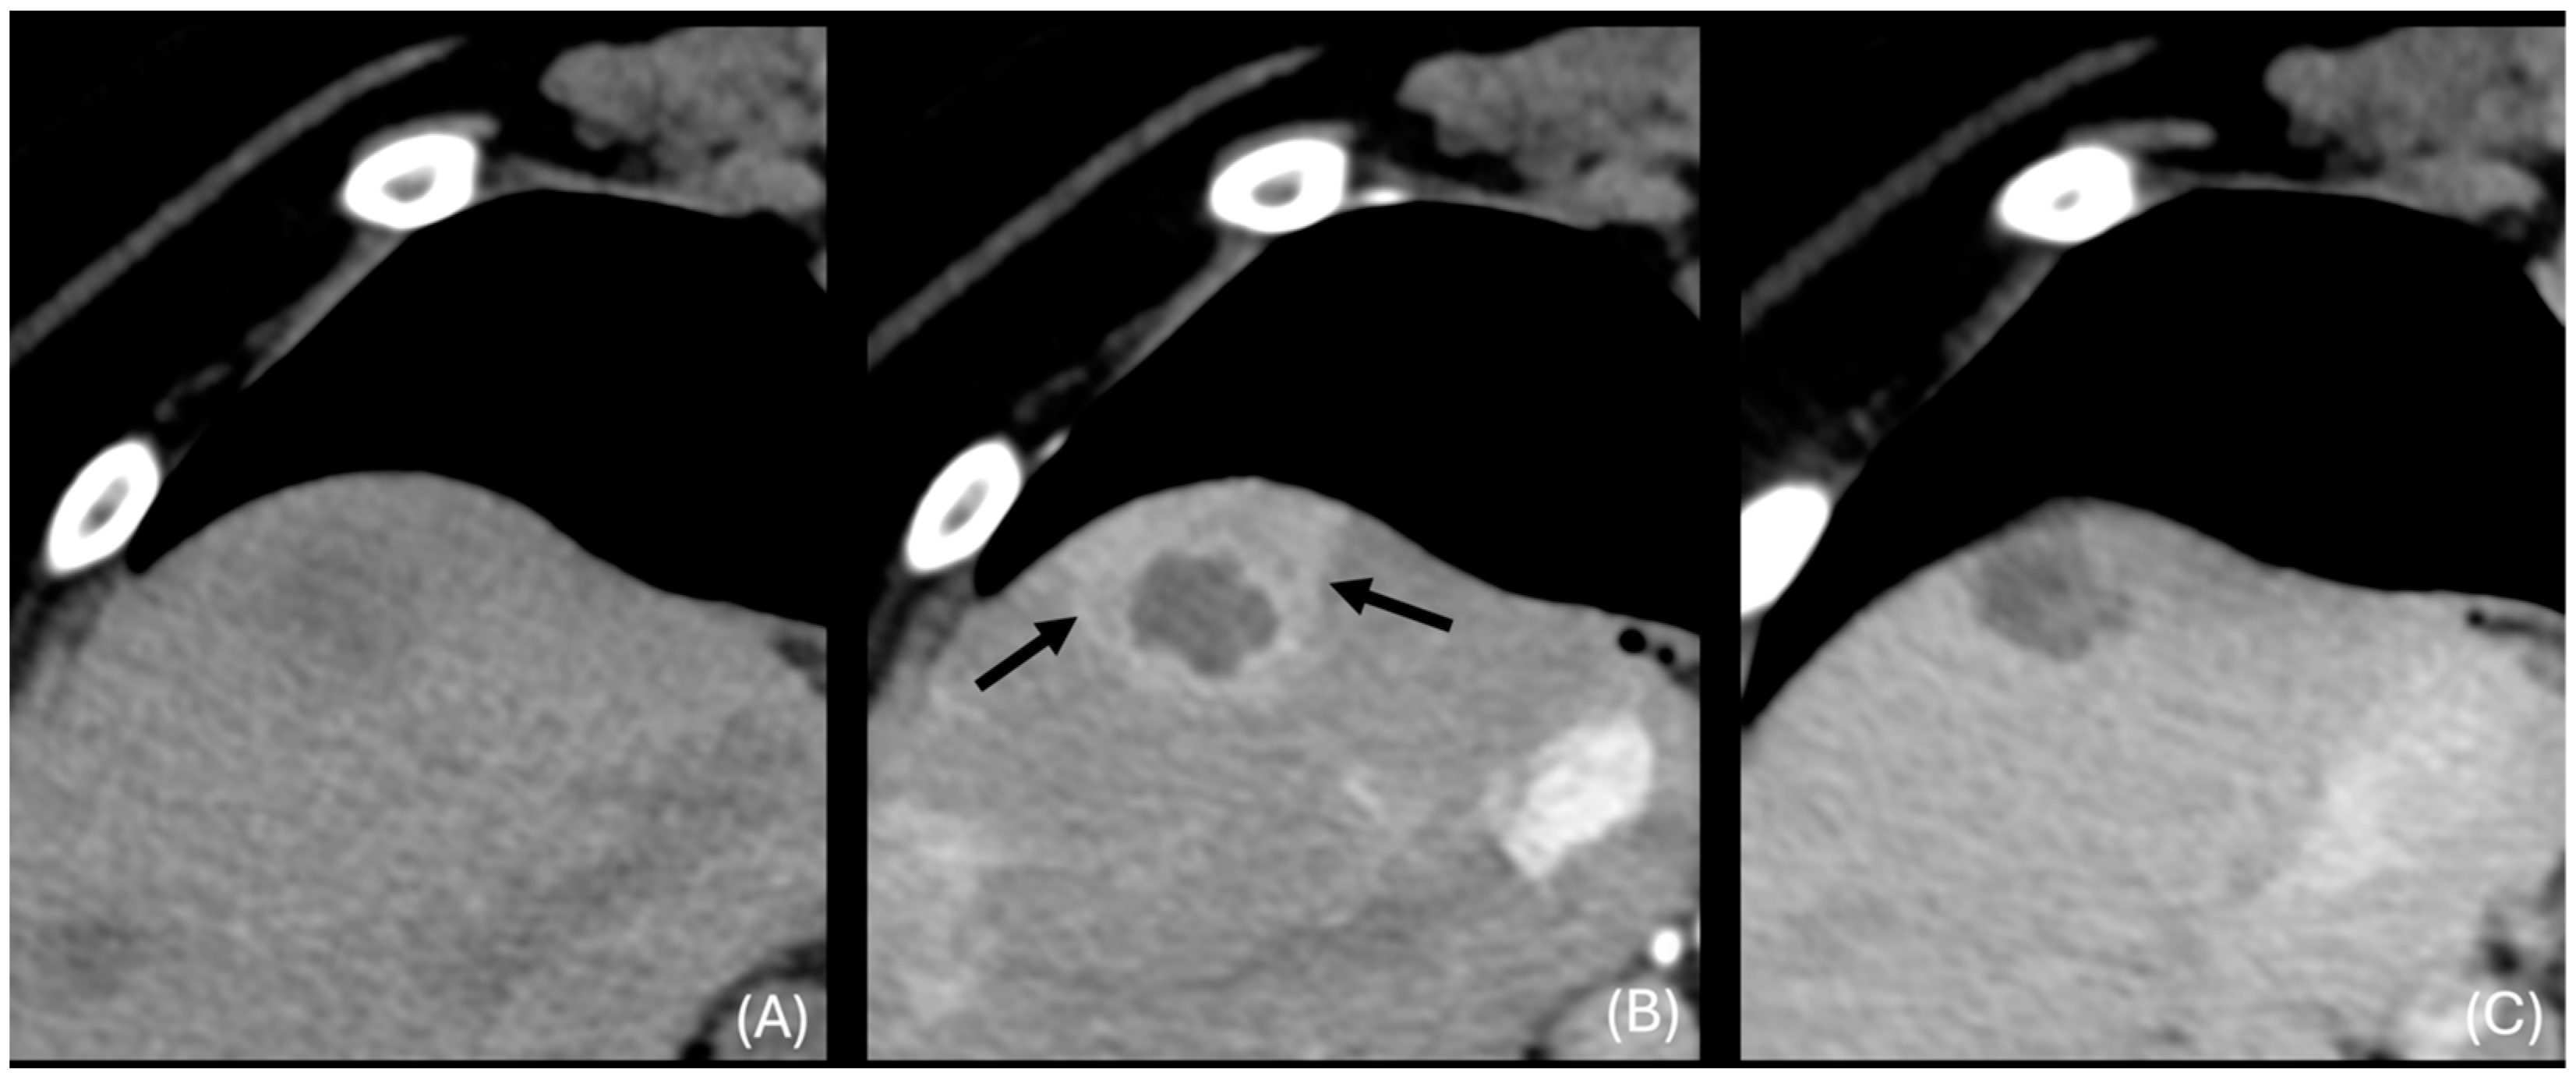

3.6.2. “Discrete” Changes